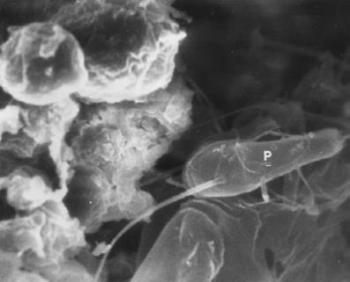

A vesekövek a kelyhekben, a pyelonban képződnek, előfordulnak pár mm nagyságúak és az egész üregrendszert kitöltő, 5–7 cm-es öntvényszerű képződmények. Kémiailag kalciumoxalát, kalciumfoszfát, magnézium-ammónium oxalát (struvit), húgysav, elvétve aminosav (cisztein) tartalmúak. Metszéslapjuk koncentrikus, a rétegek eltérő összetételűek lehetnek. A vese- és hólyagkövekben identifikálhatók a húgyutakat fertőző és a kőképződést megindító kórokozók (Nickel és mtsai 1985, Takeuchi és mtsai 1984). Előfordulásuk geológiai áreák és étkezési szokások szerint változó, a vesekő a húsfogyasztók, a hólyagkő a növényi táplálékon élők betegsége. Elsőként Bitschai (1951) az 1. dinasztia korából származó (Kr. e. 3100) kétoldali nephrolithiasist írt le vázleletben. Afrika más részein, a római garnizonok temetőiben és a hottentották területein egyaránt leltek veseköveket (Steinbock 1989). Európaszerte kerültek elő vesekövek a vaskor kezdetétől (Kr. e. 500 körül). Amerikában egy ősindián telepen (Kr. e. 3500–3000) bukkantak a legrégebbiekre (Steinbock 1989). Chilei múmiában ureterbe beékelődött követ észlelt Gerszten és mtsa (1995). Hazánkban nem ismertettek vesekövet régészeti anyagban. Az 1780-ban elhunyt, 68 éves váci férfi múmia boncolásakor találtam féloldali nephrolithiasist. A kő 35x22x20 mm nagyságú (129. ábra), 34 g súlyú, kémiailag kalcium foszfátot, kalcium karbonátot és magnézium-ammónium foszfátot tartalmazott, struvit, apatit és whitlockit kristályok formájában. Elektronmikroszkóppal sok fehérvérsejtet, vesemedencei hámsejteket, fibrinszálcsákat és kevés, olykor csillós pálcát láttam (130. ábra, 131. ábra, 132. ábra). Az ilyen összetételű és kristályszerkezetű kövek főként akkor alakulnak ki, ha a vesemedence gyulladását Proteus baktérium okozza.

132. ábra. Csillós baktérium, feltehetően Proteus mirabilis (P)a vesekőben. SEM 10200× nagyítás